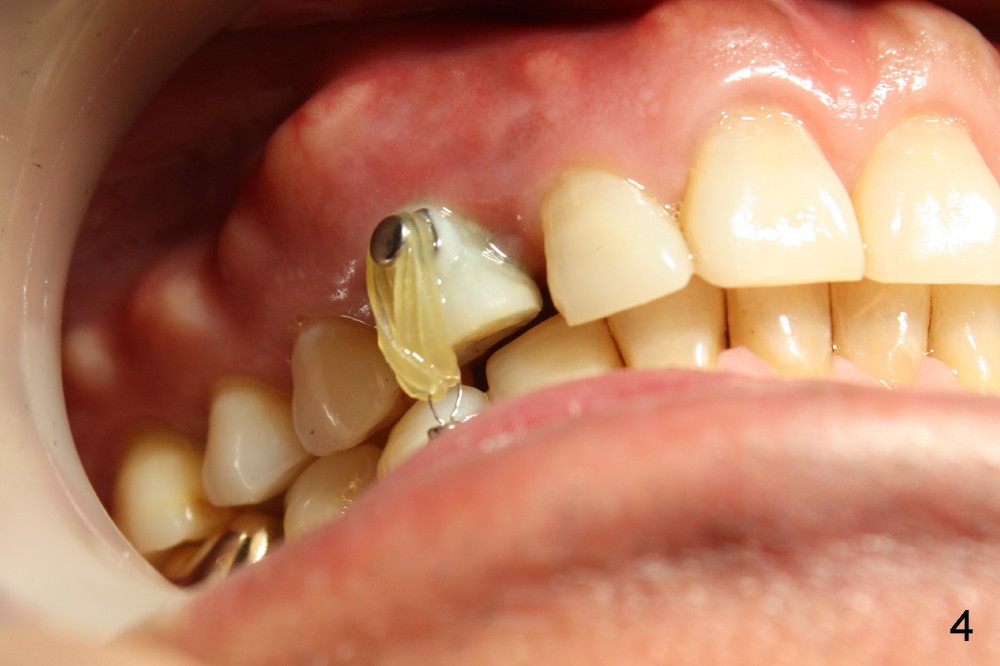

A 1.6x6 mm mini-implant was placed between #27 and 28 on 02/20/2014 (Fig.1,2). The major problem is its angulation. A 1/4 elastic cannot be placed over it. Instead a ligature wire is used to hold the elastic in place (Fig.3,4, taken 2 months later). Occlusal reduction is done (Fig.4), which alleviates the discomfort. But the extrusion is not obvious, since retraction is not 24 hours. The elastic and wire needs replacement quite often, which is not patient friendly. The extraoral Bitewing is taken 2.5 months post implantation (Fig.5). The tooth #6 has a long root. What should we do?